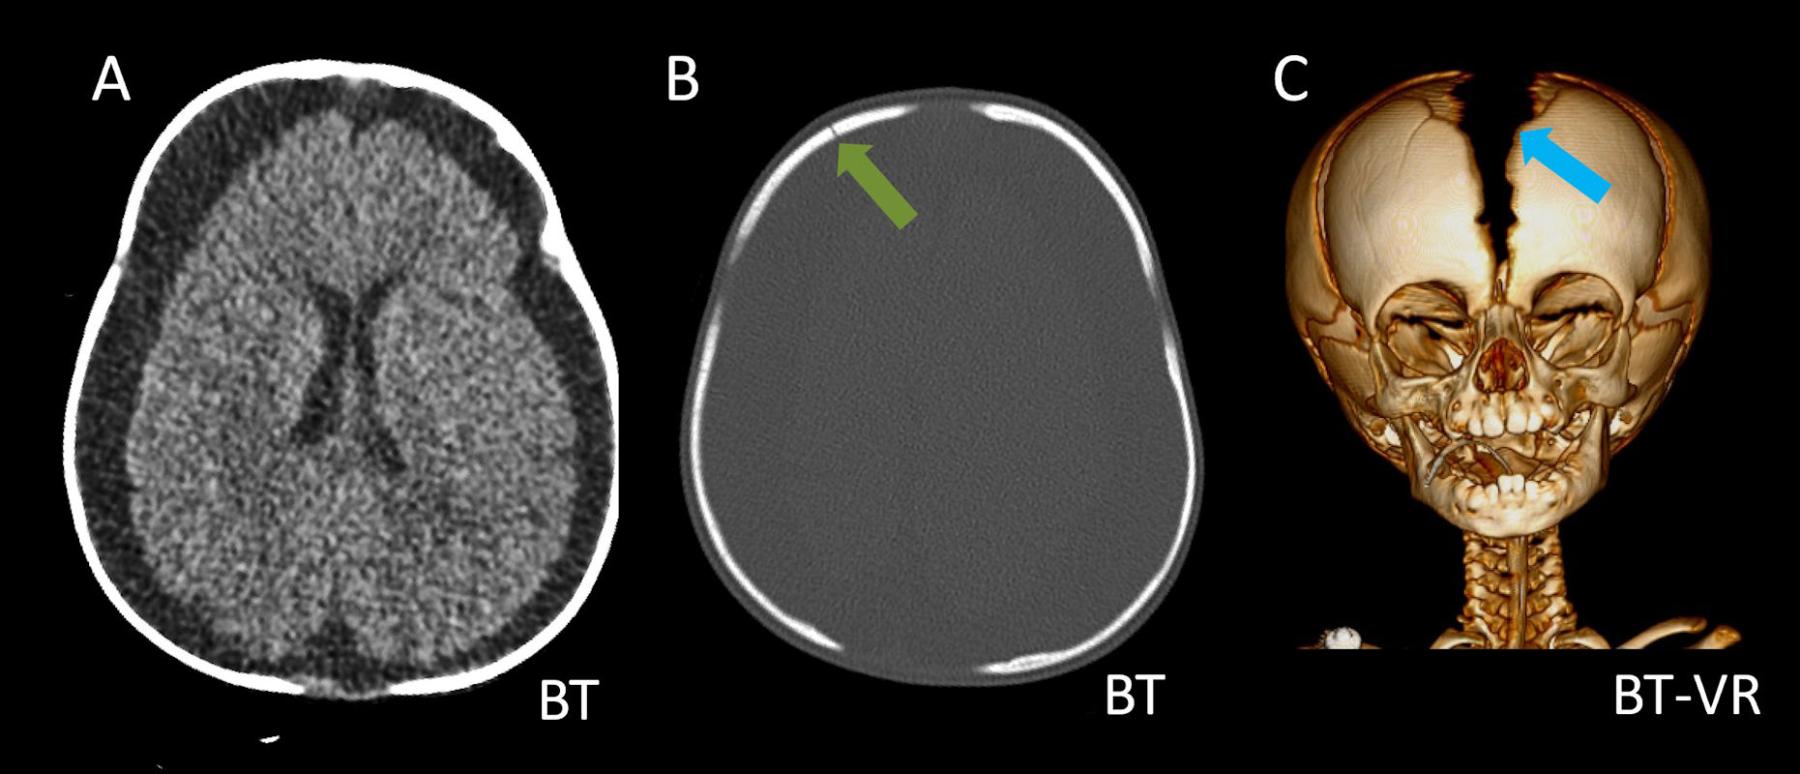

- A) Bilateral serebral konveksitede subdural higroma

- B) Kemik pencerede frontal kemikte sağda nondeplase kırık

- C) Süturlarda ayrışma

- D) Posteriyor fossada subdural hemoraji

- Kalvaryal kırıklar: Tek başına istismar ilişkili kafa travması açısından spesifik olmasa da çoklu kırıklar istismara bağlı travma şüphesini artırır.